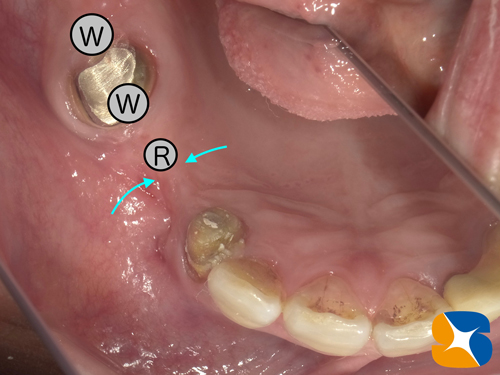

R…細みのインプラントサイズ予定

W…太めのインプラントサイズ予定

水色の2箇所の予定場所(=写真=)の中間位置に太めにインプラントを移植することにしました。